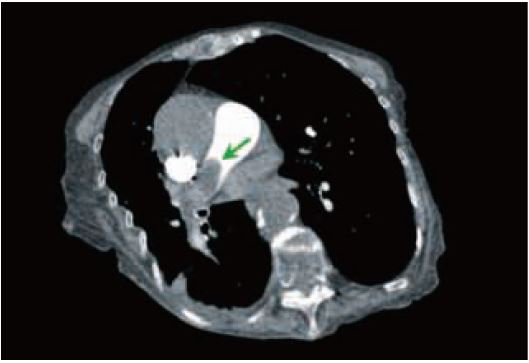

Рис. 4 Звичайна ангіографія – ІМТ 26,80 kVp. 45 мл ніопаму 370 при 3 мл/с. Доза 1,3 мЗв. Множинні правобічні емболії легеневої артерії (стрілки).

Рис. 5 КТ-ангіографія з вільним диханням та одним обертом – 80 кВ. 30 мл ніопаму 370 при 3 мл/с. Доза 0,5 мЗв. Велика емболія легеневої артерії закупорює праву легеневу артерію (стрілка).